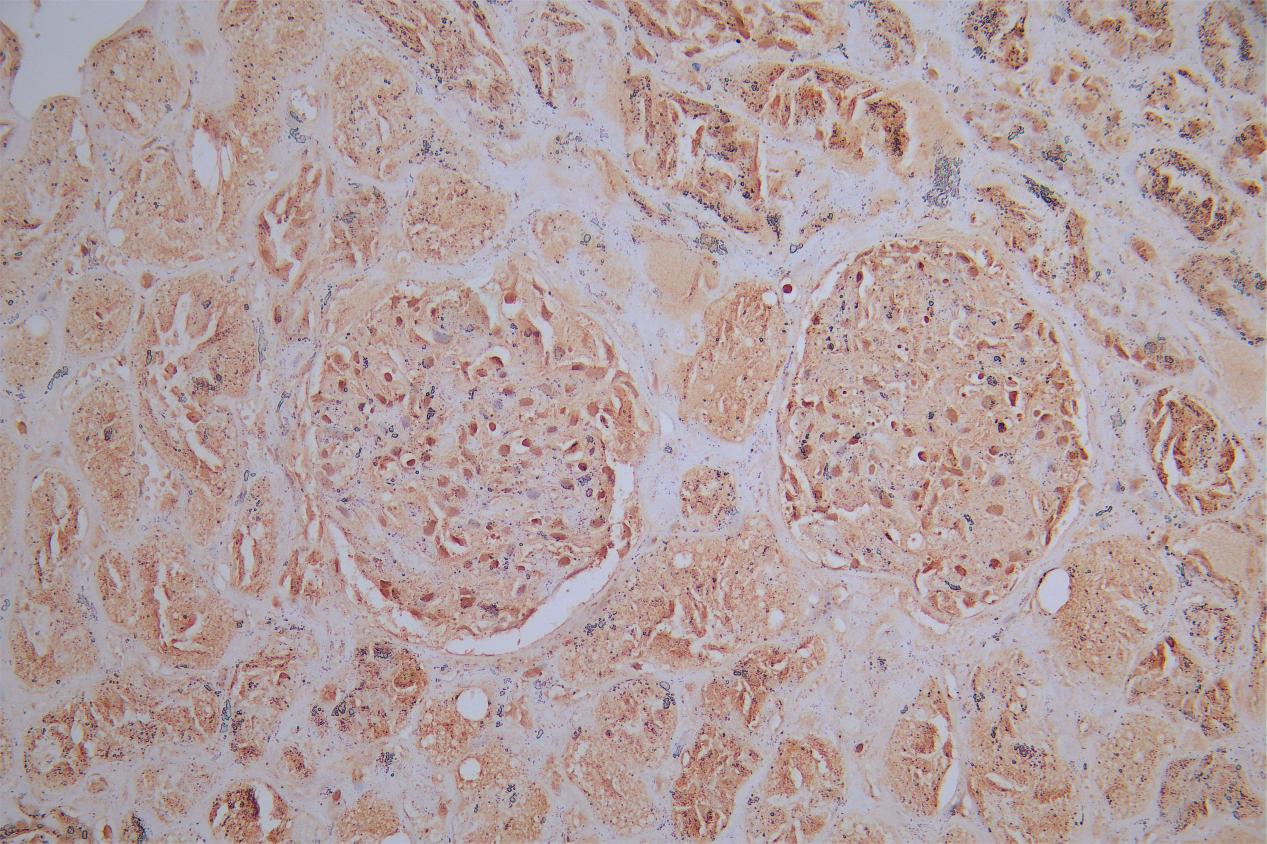

IHC image of CSB-PA865160LA01HU diluted at 1:180 and staining in paraffin-embedded human kidney tissue performed on a Leica BondTM system. After dewaxing and hydration, antigen retrieval was mediated by high pressure in a citrate buffer (pH 6.0). Section was blocked with 10% normal goat serum 30min at RT. Then primary antibody (1% BSA) was incubated at 4°C overnight. The primary is detected by a Goat anti-rabbit polymer IgG labeled by HRP and visualized using 0.05% DAB.